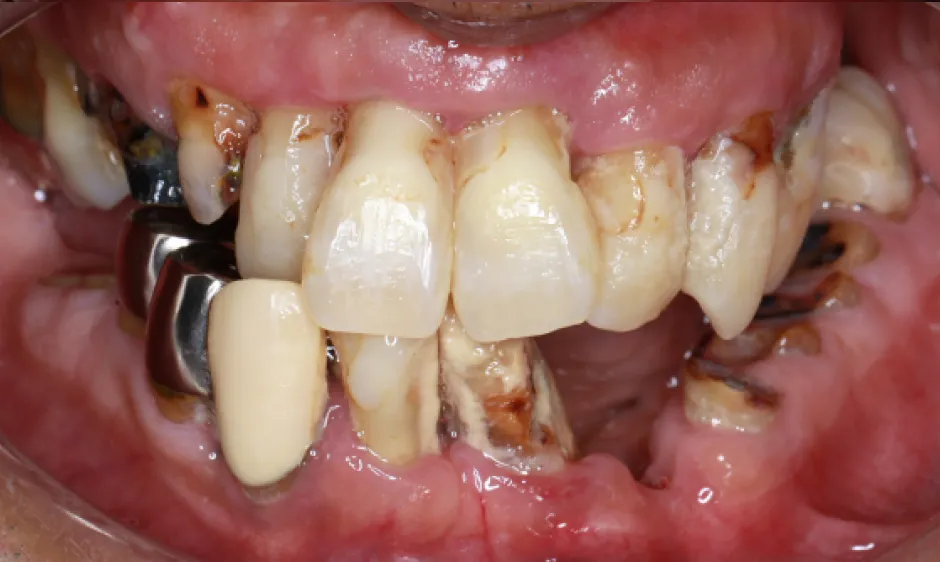

03歯がボロボロの方への

全顎治療むし歯や歯周病が広がり、「どこから治せばいいのか分からない」状態は、痛みだけでなく食事や会話、見た目のストレスにもつながります。医療法人大杉歯科医院では、まず精密に検査し、残せる歯・治療が必要な歯を見極めたうえで、治療の優先順位を整理します。仮歯で噛み合わせを整えながら、補綴やインプラントなどの選択肢を組み合わせ、機能と審美の両立を目指します。

いきなり理想を押しつけるのではなく、現実的に続けられる計画で、お口全体を立て直す治療をご提案します。症例1

- 治療名

- 重度虫歯からの全顎インプラント治療

- 患者様

- 70代男性

- 執刀医

- Dr. 大杉

- 治療期間

- 1年6ヶ月

- 治療費

- 上顎:4,620,000円(税込)

下顎:3,630,000円(税込) - リスク

- ラミックのすり減りを防ぐために、ナイトガードを作成しています。毎晩使用することで、セラミックを長持ちさせることができます。

症例2

- 40代男性

- 1年

- 上顎:3,630,000円(税込)

- 術後、硬い物を食べないでください。

インプラントが骨に結合するまで2ヶ月かかります。

この期間中に強い負荷をかけると、結合しないことがあります。